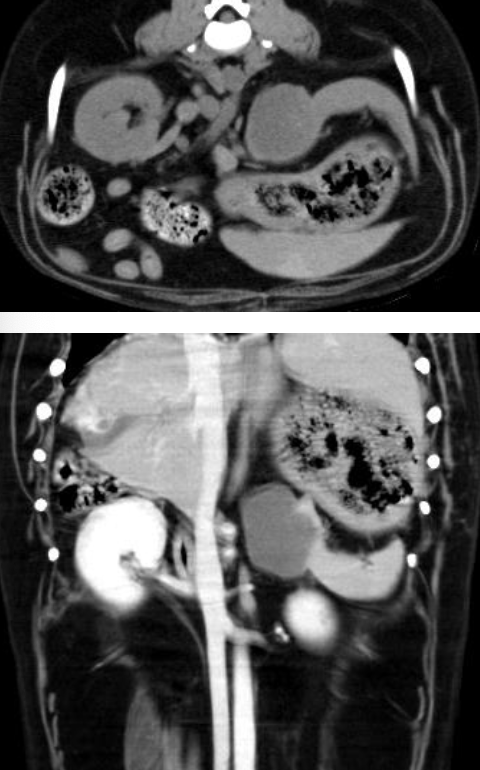

what diagnostic imaging modalities are used to diagnose hemangiosarcoma?

-thoracic imaging (radiographs or CT)

-abdominal imaging (radiographs, ultrasound, or CT)

-echocardiogram